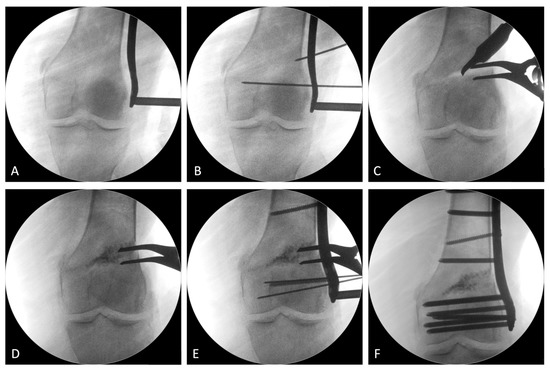

ゼロからはじめる! Knee Osteotomyアップデート | 日本 Knee。A. Stage 2 lateral knee osteoarthritis with HKA of 193。Functional and Radiographic Results of Arthroscopy-Assisted。膝の骨切り術に関する最新情報を提供する専門書。Functional and Radiographic Results of Arthroscopy-Assisted。裁断済みです。。定価12000